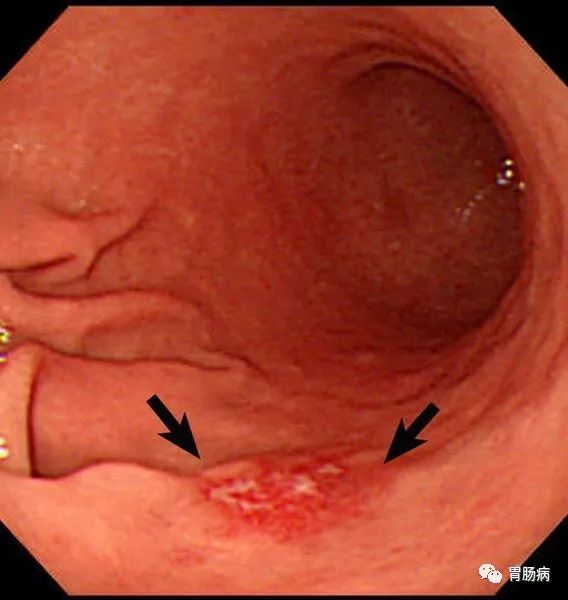

张先生,42岁,职员,无任何消化道症状,单位例行体检,发现胃体一处几毫米的粘膜改变(下图黄圈处)。

病理证实:高级别上皮内瘤变(早期癌)。

因为是极早癌,内镜下切除术,完全就能够根治。这是张先生不幸中的万幸。目前张先生早已康复,只需要定期胃镜复查即可,几乎不会影响他的自然寿命。

早期胃癌胃镜图片

胃镜可以直观的观察胃内病变的形态,病理组织学检查能够观察细胞形态的变化,两者结合对胃癌的确诊率达98%以上。

更重要的是,胃镜结合染色检查能更多的发现早期胃癌。

早期的胃癌不仅能够通过胃镜进发现,甚至可以通过它进行切除。病灶大小于等于2 cm、无合并溃疡的分化型黏膜内癌,胃黏膜高级别上皮内瘤变,可通过胃镜进行切除。